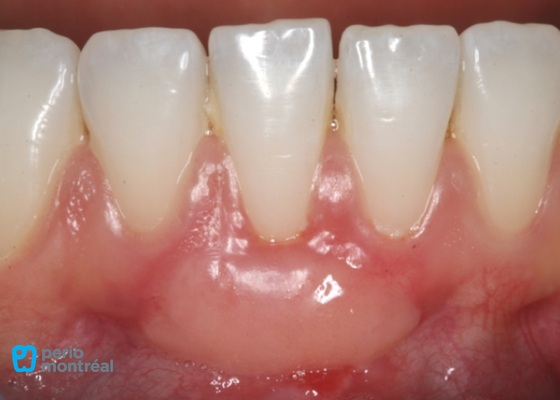

Pre-Op and Post-Op Pictures

- PRE-OPÉRATOIRE

- POST-OPÉRATOIRE

Final result

Our primary goal of increasing the width of keratinized tissue is achieved, and we are able to get almost 100% root coverage as well in one surgical procedure. Both the patient and surgeon were very happy with the result!